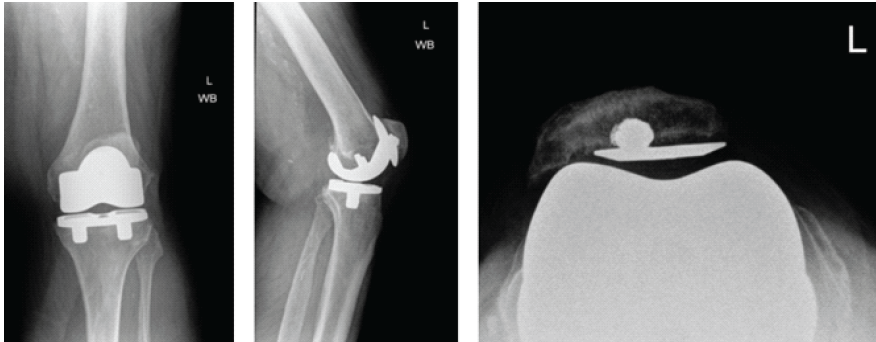

A post-operative X-ray showed the knee to be in appropriate alignment without evidence of complication (Fig. 2). The patient was transferred to the post-anesthesia care unit (PACU) in good condition, having tolerated the procedure well. Due to the patient’s high quality bone and relatively young age, a press-fit implant was chosen over the more traditional cemented implant, including: A standard width, size 8, Zimmer Persona CR Press-Fit Femoral Component, a size F, 2 peg, Press-Fit, Zimmer Persona tibial baseplate, a size 10 Zimmer Persona Medial Congruent Polyethylene Insert, and a size 38 Zimmer NexGen Press-Fit Patella. The patient continued to present for routine follow-up without evidence of complication for nearly 2 years until he returned to the clinic, stating that he had never been pleased with the operation. He complained of pain while standing, and at times, a sensation of “catching” and “giving out”. The patient underwent a normal physical exam. Three radiographic views of the left knee were examined for potential abnormalities. AP, lateral, and patellofemoral views of the left knee at this time demonstrated a failed patellar component with a shear fracture of the single peg prosthesis (Fig. 3). These findings were shared and discussed with the patient, who agreed to proceed with revision of the patellar component.

Figure 3: Second post-operative X-rays. Three views of the left knee are visualized at this post-operative visit, including anteroposterior, lateral, and patellofemoral views, respectively. These radiographs demonstrate a broken patellar component with a shear fracture of the single peg prosthesis. The femoral and tibial components appear well fixed and positioned.